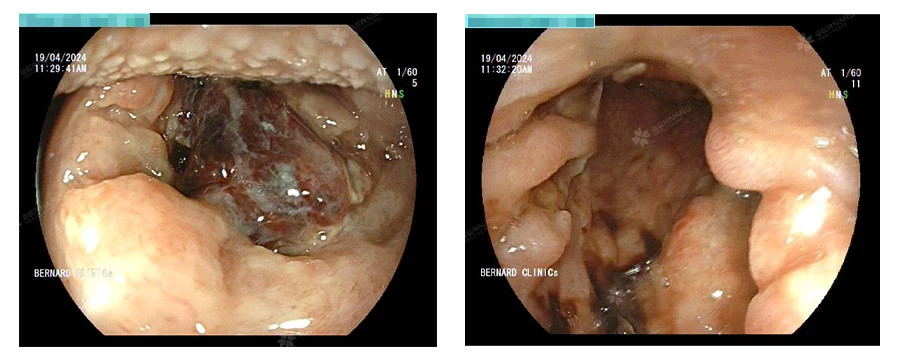

Theo Bác sĩ CKI. Lưu Tú Anh - Chuyên khoa Tai Mũi Họng, Bernard Healthcare, người bị viêm mũi xoang cấp, viêm xoang mạn tính; người bị trào ngược dạ dày - thực quản, người có tiền sử gia đình mắc ung thư vùng đầu mặt cổ nên khám định kỳ và thực hiện nội soi tai mũi họng khoảng 4 - 12 tháng/lần. Nội soi giúp phát hiện các triệu chứng bất thường ở tai mũi họng, kể cả ung thư.